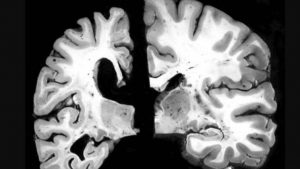

Generalmente el Alzheimer es frecuente en las personas mayores de setenta años, la causa que la produce es desconocida, sin embargo, los factores genéticos son determinantes en la enfermedad, las células cerebrales se degeneran y se destruyen, apareciendo en el cerebro placas seniles y haces neurofibriliares que son identificados durante la autopsia.